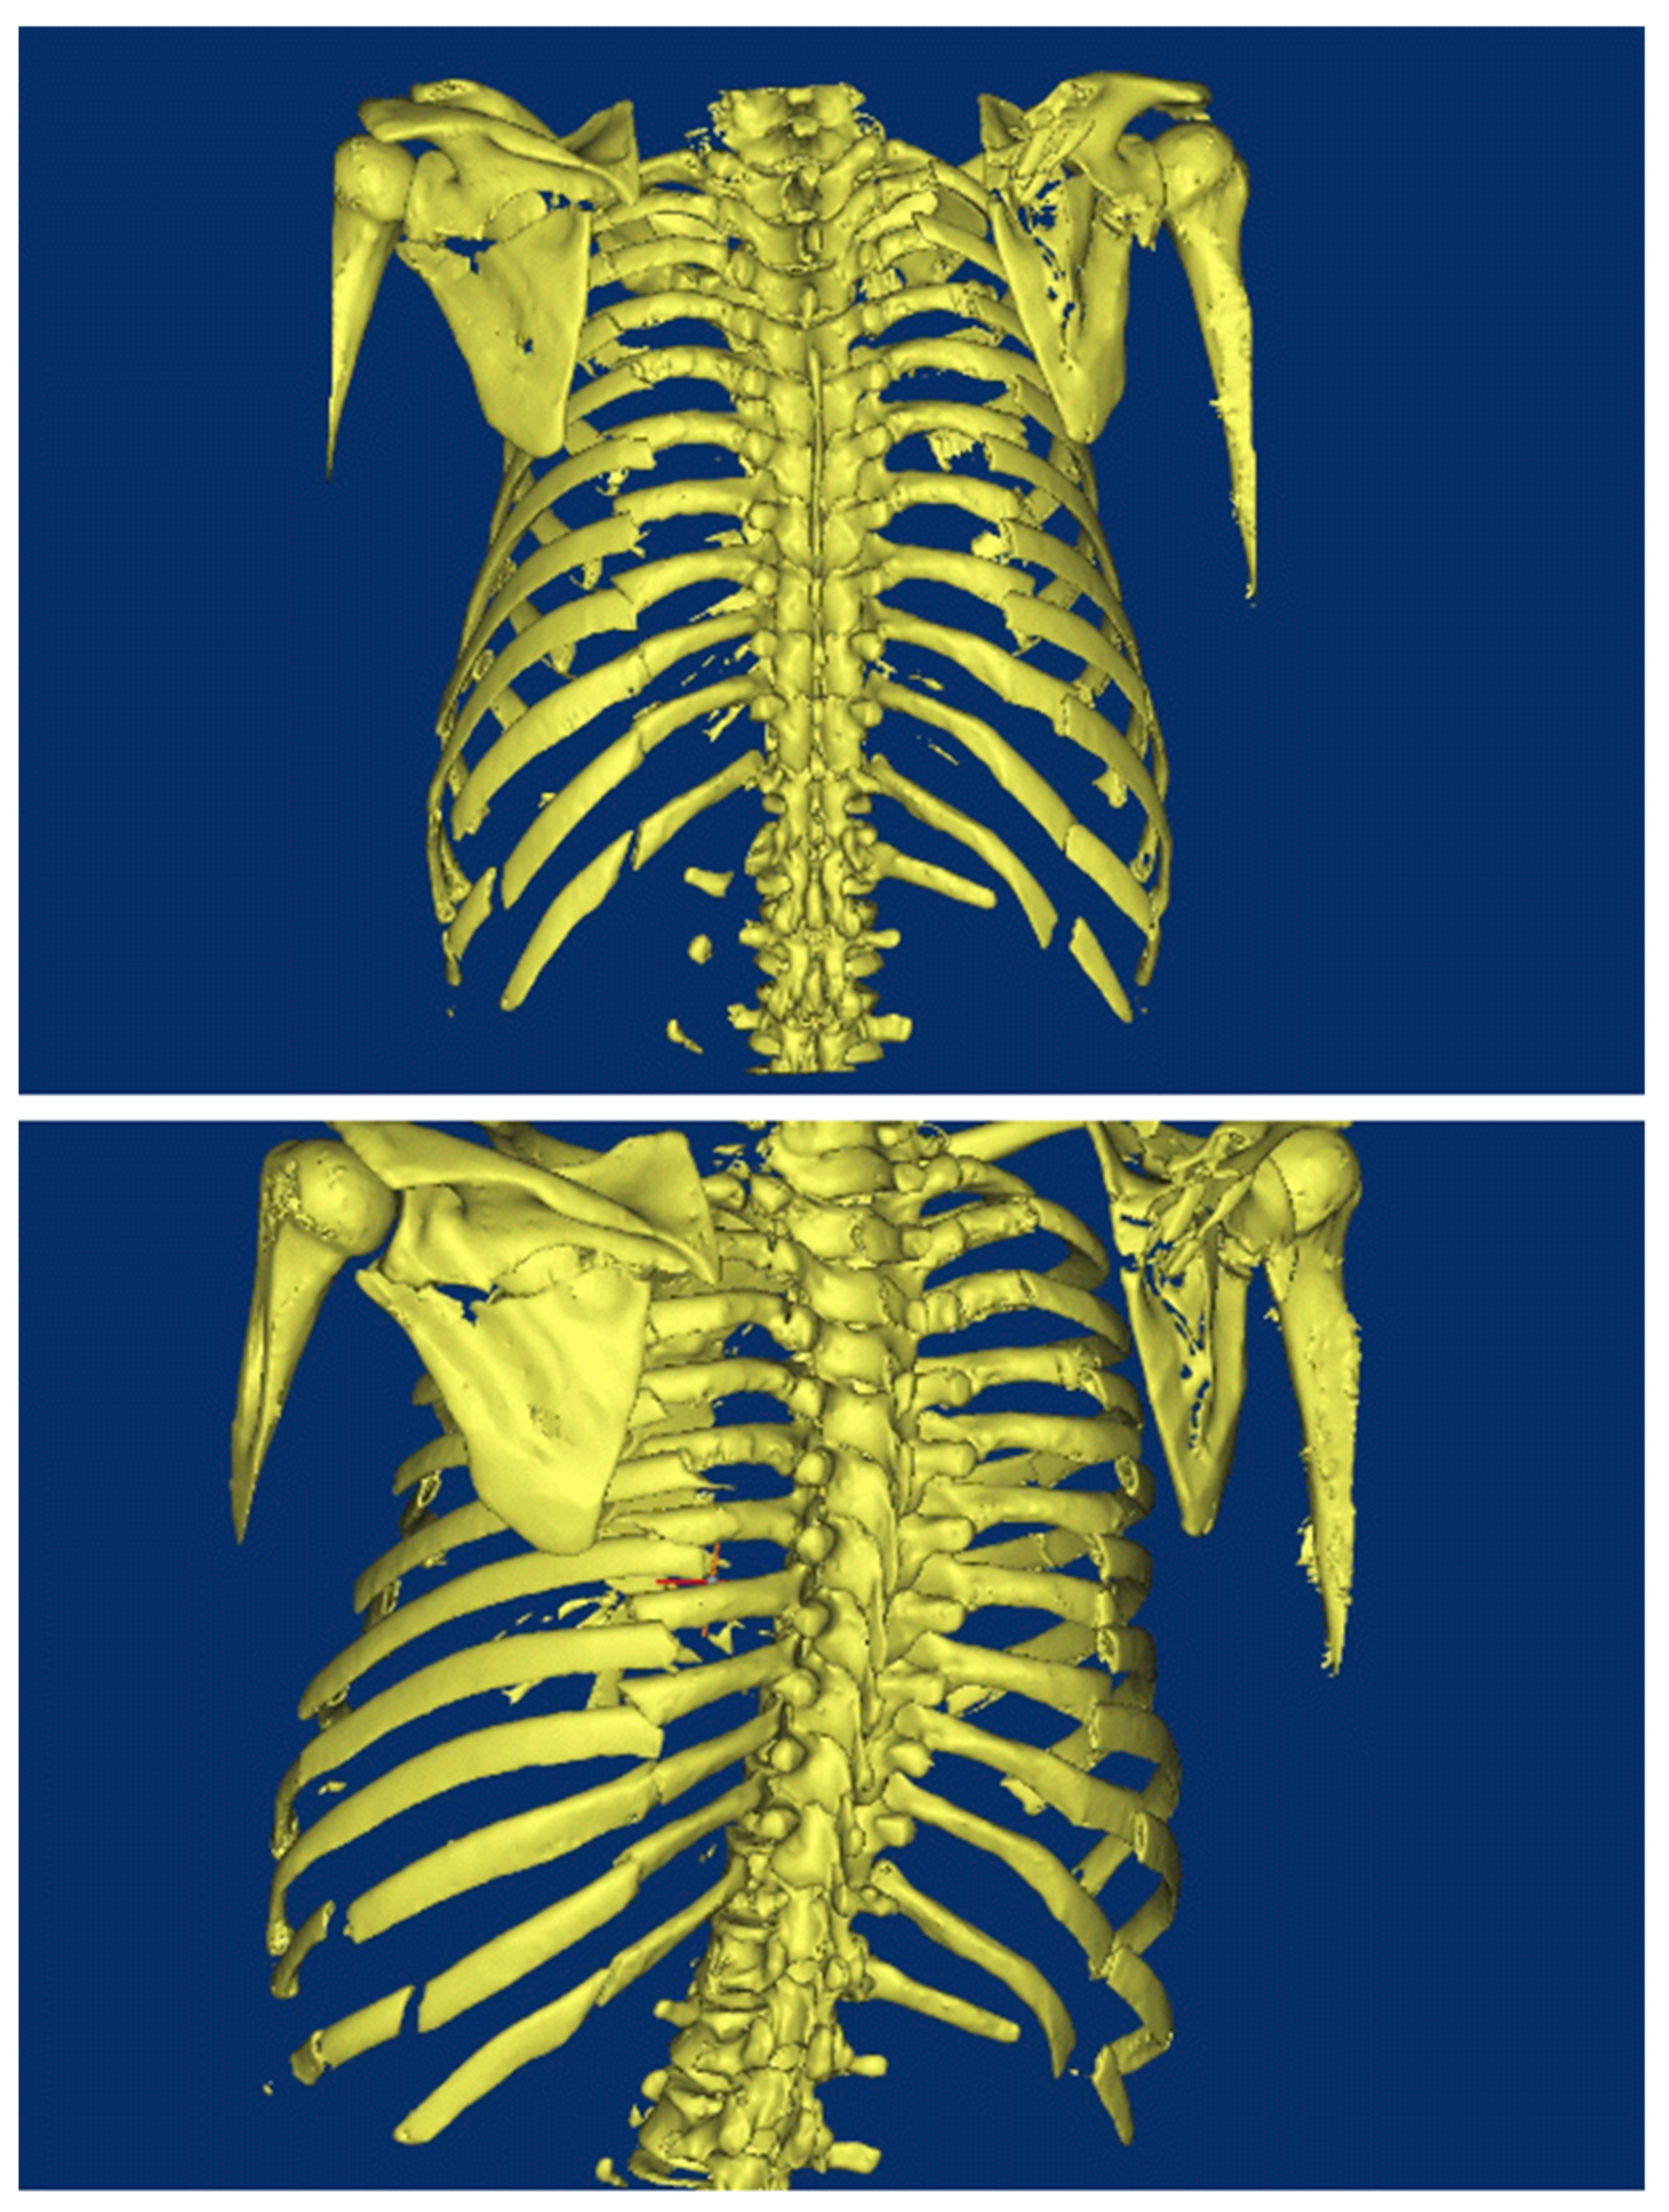

2. Background of Damaged Human Body

3. Reconstruction of the Damaged Human Model